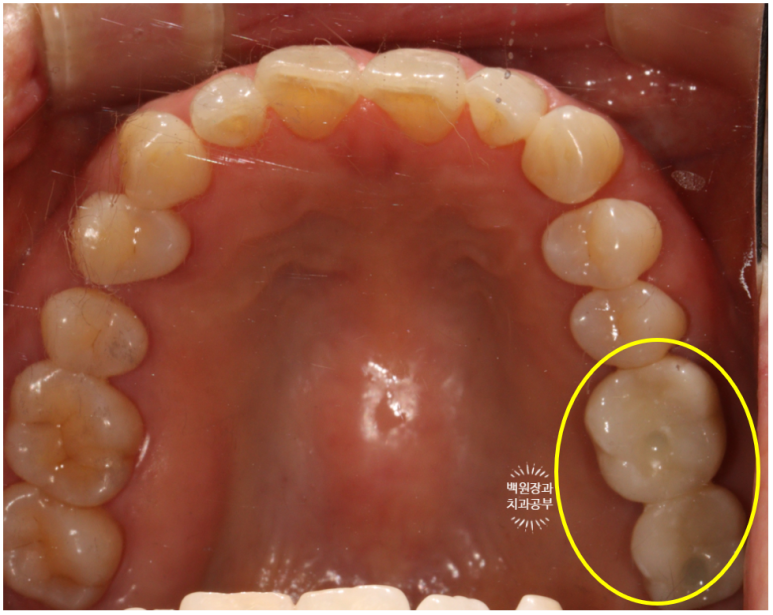

3개월의 치유기간을 가진 후 보시는 바와 같이 새로이 보철물을 제작해 드렸습니다.

약간 이상적이지 않은 형태 같아 보이실 수 있지만!?

입안에서 본 사진 상에서는 상당히 이상적인 지르코니아 크라운 형태로

제작이 잘 되었다는 것 !!